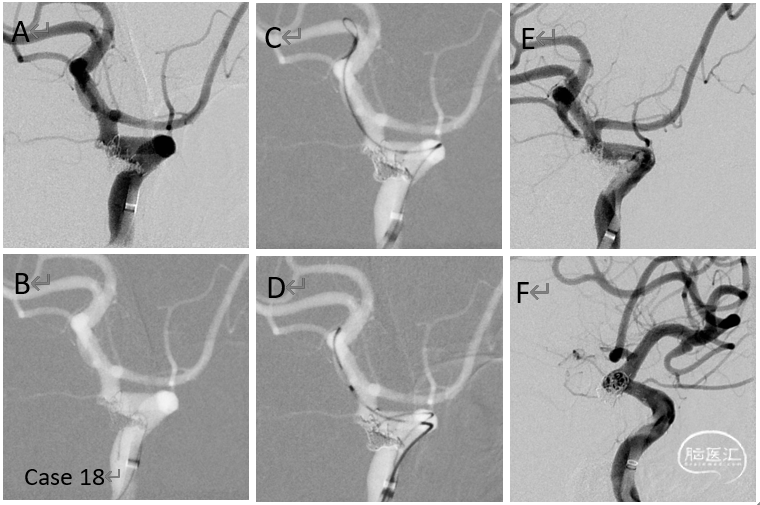

病例16

多发狭窄、闭塞、闭塞前病变,介入似乎没有啥可做的工作。重新DSA评估后发现颈外到颅内新的天然代偿通道,给予右侧颈总动脉狭窄球囊扩张术,术后脑膜中动脉后支向颅内的血供范围明显增加。术后患者自诉:头不晕了,眼睛看东西也清楚了,脑袋也轻松通透了。

病例17

颈内动脉起始部重度狭窄球囊扩张支架植入术

病例18

后交通动脉瘤复发再治疗